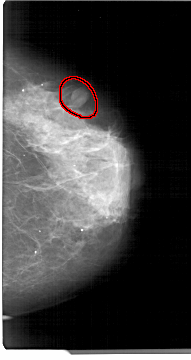

A_1305_1.RIGHT_MLO

RIGHT_MLO LINES 5491 PIXELS_PER_LINE 3241 BITS_PER_PIXEL 12 RESOLUTION 43.5 OVERLAY

FILE: A_1305_1.RIGHT_MLO.OVERLAY

TOTAL_ABNORMALITIES 1

ABNORMALITY 1

LESION_TYPE MASS SHAPE OVAL MARGINS CIRCUMSCRIBED

ASSESSMENT 4

SUBTLETY 4

PATHOLOGY BENIGN

TOTAL_OUTLINES 1

BOUNDARY